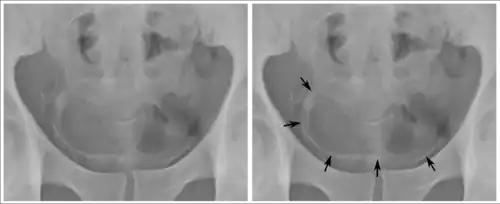

Orina

El examen de orina se recomienda sólo para S. haematobium. Una vez centrifugada la muestra de orina, el sedimento resultante se filtra con membranas Nucleopore ® y se procede al recuento de huevos sobre la misma. El diagnóstico puede complementarse con los rayos X de la zona pélvica, con el fin de localizar calcificaciones típicas de una infección crónica.